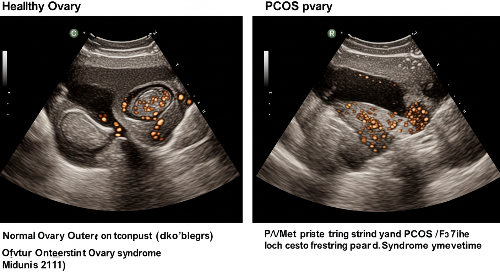

- 다낭성 난소 형태 → 초음파 검사에서 난소에 여러 개의 작은 낭종(난포)이 관찰됨

3) 초음파 검사에서 다낭성 난소 형태 → 난소에 12개 이상의 작은 낭종(난포) 관찰

1) 초음파 검사 → 난소 크기 및 난포 개수 확인